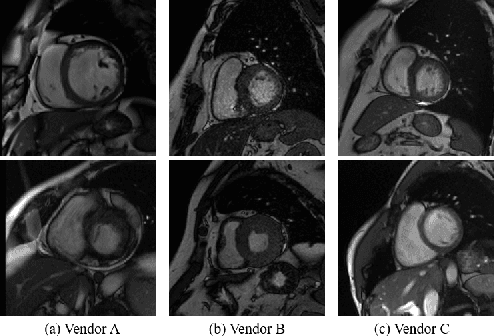

Convolutional Neural Networks (CNNs) have achieved high accuracy for cardiac structure segmentation if training cases and testing cases are from the same distribution. However, the performance would be degraded if the testing cases are from a distinct domain (e.g., new MRI scanners, clinical centers). In this paper, we propose a histogram matching (HM) data augmentation method to eliminate the domain gap. Specifically, our method generates new training cases by using HM to transfer the intensity distribution of testing cases to existing training cases. The proposed method is quite simple and can be used in a plug-and-play way in many segmentation tasks. The method is evaluated on MICCAI 2020 M\&Ms challenge, and achieves average Dice scores of 0.9051, 0.8405, and 0.8749, and Hausdorff Distances of 9.996, 12.49, and 12.68 for the left ventricular, myocardium, and right ventricular, respectively. Our results rank the third place in MICCAI 2020 M\&Ms challenge. The code and trained models are publicly available at \url{https://github.com/JunMa11/HM_DataAug}.